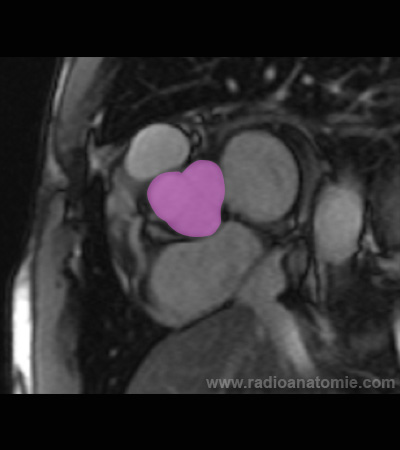

Radioanatomie et plans de coupe en IRM cardiaque

Oreillette gauche